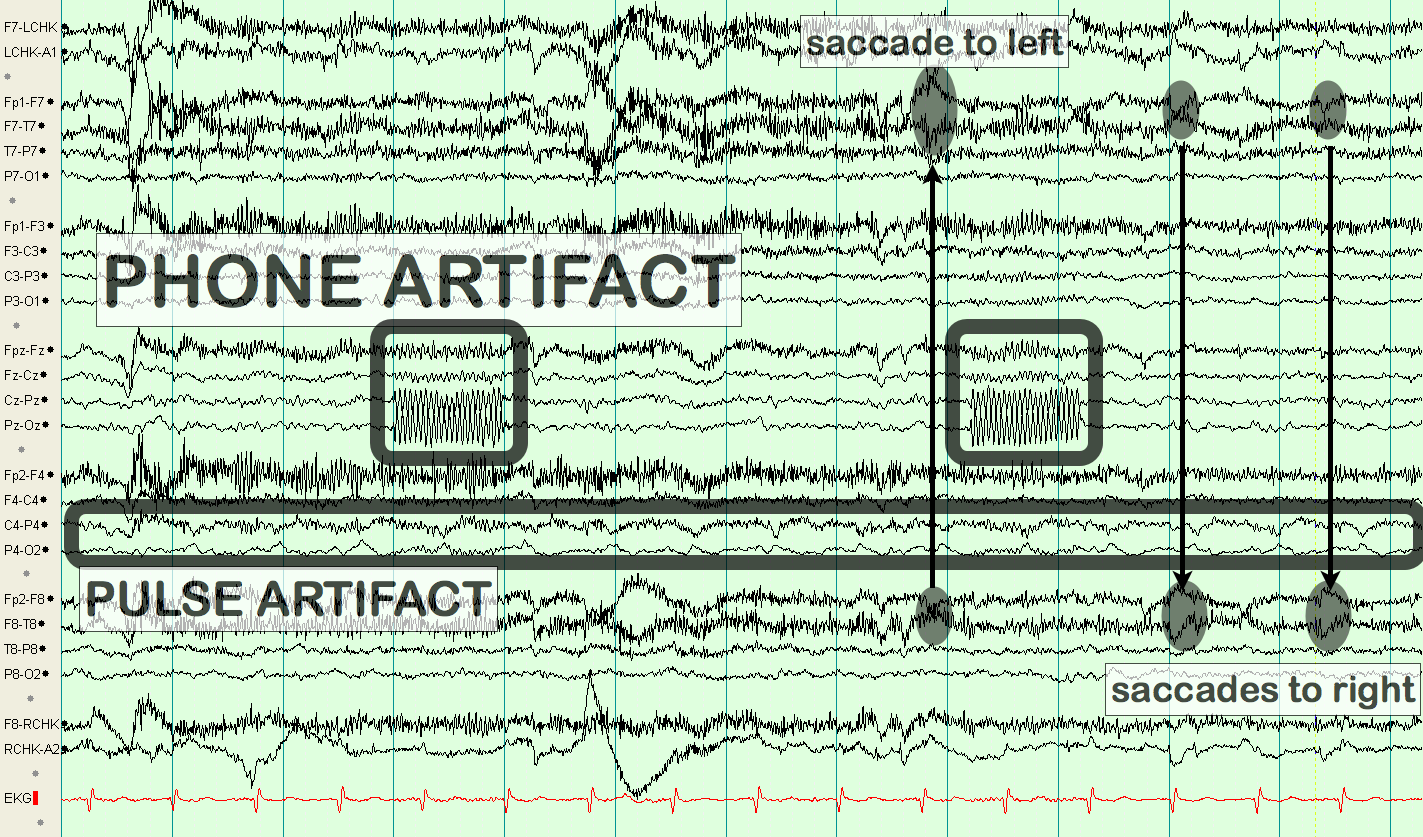

Roving Eye Movements

eegatlas-online.com

eegatlas-online.com

artifacts eye roving movements eegatlas online

| Lateral Eye Movements And Eye Blinks Recorded Simultaneously With

www.researchgate.net

www.researchgate.net

movements blinks recorded simultaneously eog bipolar

Lateral Eye Movement Although A Horizontal, Frontal Dipole Is The Key

www.pinterest.com

www.pinterest.com

eye movement eeg lateral horizontal key bullet journal

Lateral Eye Movement

eegatlas-online.com

eegatlas-online.com

artifacts eye movement lateral eegatlas online

Lateral Eye Movement

eegatlas-online.com

eegatlas-online.com

eye lateral movement artifacts eegatlas online

Lateral Eye Movement

eegatlas-online.com

eegatlas-online.com

artifacts eye movement lateral eegatlas online

Lateral Eye Movement

eegatlas-online.com

eegatlas-online.com

eye movement lateral artifacts online eegatlas